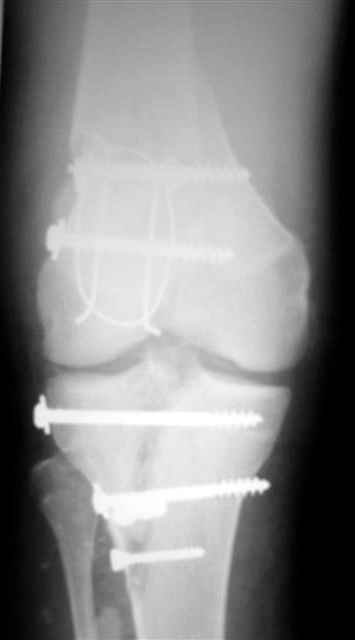

В первом письме я упомянул о закрытом повреждении правого голеностопного сустава, эверсионно-пронационный механизм травмы - перелом внутренней лодыжки( поперечный, на уровне суставной щели) и отрывной перелом бугорка Chaput. После обработки открытых переломов бедра и большеберцовой кости в эту же сессию перелом внутренней лодыжки фиксировал двумя расходящимися спицами, бугорок Chaput двумя тягловыми винтами 3,5 мм. Раны заживают благополучно. Учитывая повреждение наружной группы мышц, активное разгибание в голеностопном суставе ограничено. Пассивная + пассивно-активная мобилизация голеностопного сустава с физиотерапевтом.

Я предупреждал, что ничего сверхъестественного. Каюсь, что одна из спиц прошла несколько дальше, чем нужно было, но главное - перелом стабилизирован и больной работает суставом в полном объёме, несмотря на представленную раннее травму коленного сустава.